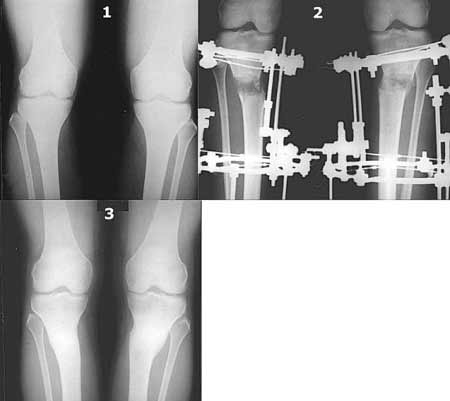

Вот ещё картинки, которые отправлял в Ортопод. Коррекция кривизны и удлинение на 3 см.

|